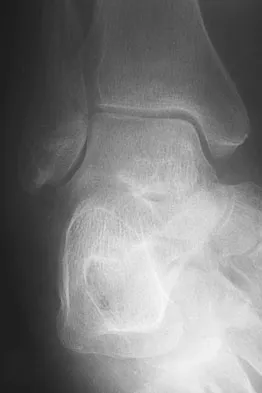

Question 64 High Yield

A 75-year-old woman began a walking program 2 months after undergoing right total knee arthroplasty. She had to stop the program after 4 weeks because of hindfoot pain and ankle swelling. Radiographs are shown in Figures 42a and 42b. What is the most likely diagnosis?

Detailed Explanation

It is often tempting to assign a diagnosis of plantar fasciitis in patients with hindfoot pain. In this patient, the radiographs confirm a diagnosis of a calcaneal insufficiency fracture. The dense condensation of bone on the lateral view confirms the diagnosis. There is no radiographic evidence of a heel spur, osteochondral lesions, or chondrocalinosis. Resnick D: Diagnosis of Bone and Joint Disorders, ed 3. Philadelphia, PA, WB Saunders, 1995, p 2591. Kearon C: Natural history of venous thromboembolism. Semin Vasc Med 2001;1:27-37.